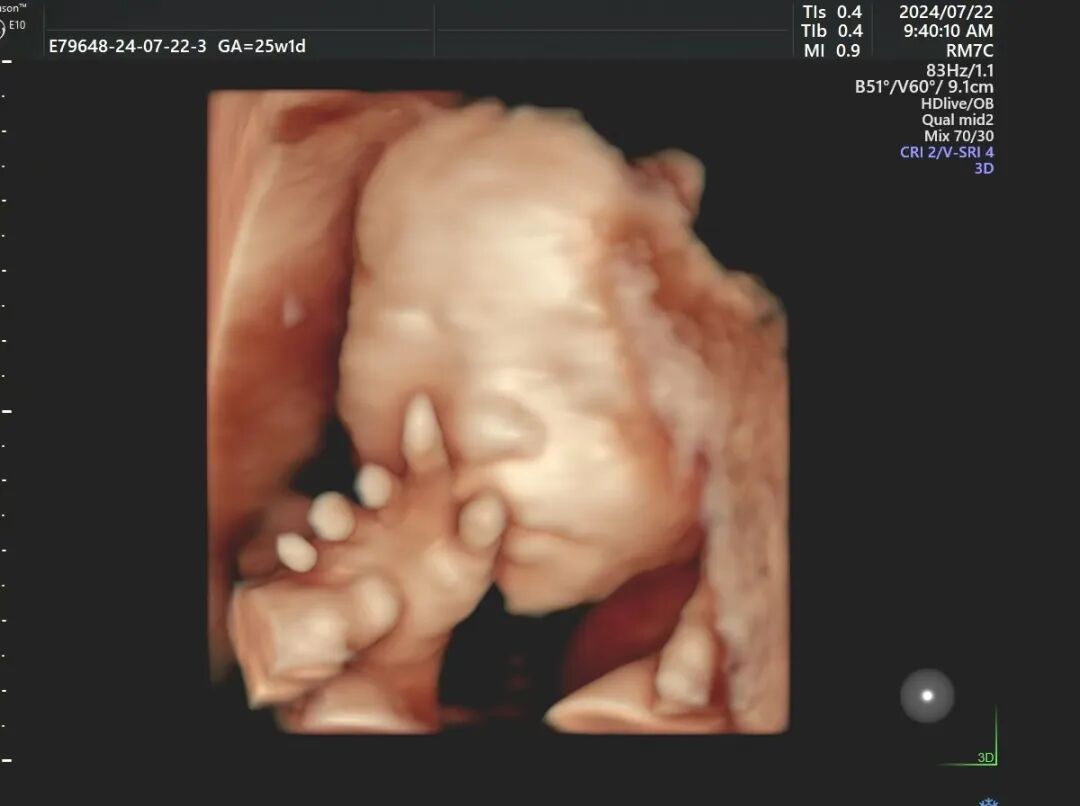

只见彩超医生把带点冰凉的、黏糊糊的耦合剂涂到小叶肚皮上,也许是肚里的小家伙也觉得有点凉,竟然在里面翻滚起来了。

不是两个手捂着脸,就是拼命抓脐带,或是老翻跟头,像是在跟大人们捉迷藏,一刻不消停。有趣的模样令人忍俊不禁,但医生却抓拍不到好的画面,只能让小叶先出去走走,看能不能把这小家伙的正脸调转过来。

这次,宝宝好像听懂话了,终于把正脸转过来了,TA长得跟小叶可真像~望着墙上的图像,小叶很激动,这一刻,她感觉辛苦都是值得的。

“我们医院采用的设备是四维E10,清晰度、性能上更强,能实时捕捉宝宝的动态画面,显示出胎儿的颜色、面、各器官,发现胎儿畸形、唇裂、腭裂、骨骼发育异常等;还有胎儿的心脏、脐带、血流变化、中枢系统及脊柱等,提供更精准、更直观的图像。”医生介绍道。